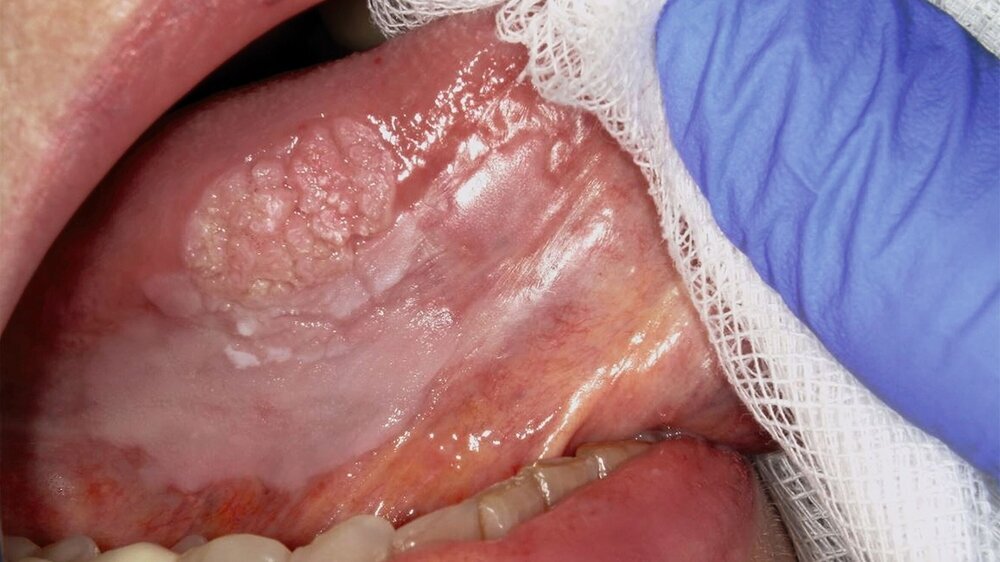

Die Leukoplakie äußert sich in Form von weißlichen Flecken oder Plaques auf der Mundschleimhaut, die nicht abgewischt werden können. Sie sind in der Regel schmerzlos, können aber durch ihre Beschaffenheit – meist rau oder leicht erhaben – auffallen. Am häufigsten sind sie an der Wangeninnenseite, am Alveolarfortsatz, an der Zunge, am Mundboden oder an den Lippen zu finden [Kämmerer et al., 2017; Speight et al., 2018]. Je nach Aussehen und histologischer Beurteilung unterscheidet man die homogene Leukoplakie von der inhomogenen Leukoplakie. Die homogene Leukoplakie zeigt sich als gleichmäßig weißer, glatter oder leicht rauer Fleck (Abbildung 1). Ihr Risiko, bösartig zu entarten, gilt als gering. Inhomogene Leukoplakien haben im Gegensatz dazu ein erhöhtes Entartungsrisiko und lassen sich in weitere Formen unterteilen: die gesprenkelte Form, auch als Erythroplakie bezeichnet (eine Mischung aus weißen und roten Arealen, wobei der weiße Anteil überwiegt), die noduläre Form (kleine, polypenartige Vorwölbungen mit rundlichen, roten oder weißen Erhebungen) und die verruköse Form (gekennzeichnet durch eine gefurchte oder warzenartige Oberfläche) (Abbildungen 2 und 3) [Kämmerer et al., 2017; Warnakulasuriya et al., 2016].

Trotz sorgfältiger Probebiopsie kann es in komplexen Fällen zu einer Diskrepanz zwischen dem histopathologischen Ergebnis und dem klinischen Befund kommen. Die S2k-Leitlinie „Diagnostik und Management von Vorläuferläsionen des oralen Plattenepithelkarzinoms in der Zahn-, Mund- und Kieferheilkunde“ empfiehlt in solchen Fällen eine erneute histologische Überprüfung oder eine Überweisung in eine entsprechende Fachklinik [van der Waal, 2009] Die Abbildungen 7 bis 9 zeigen die Entwicklung einer Leukoplakie der Zunge (Abbildung 7), ihre Transformation in ein orales Plattenepithelkarzinom (Abbildung 8) sowie den klinischen Situs nach chirurgischer Therapie (Abbildung 9).